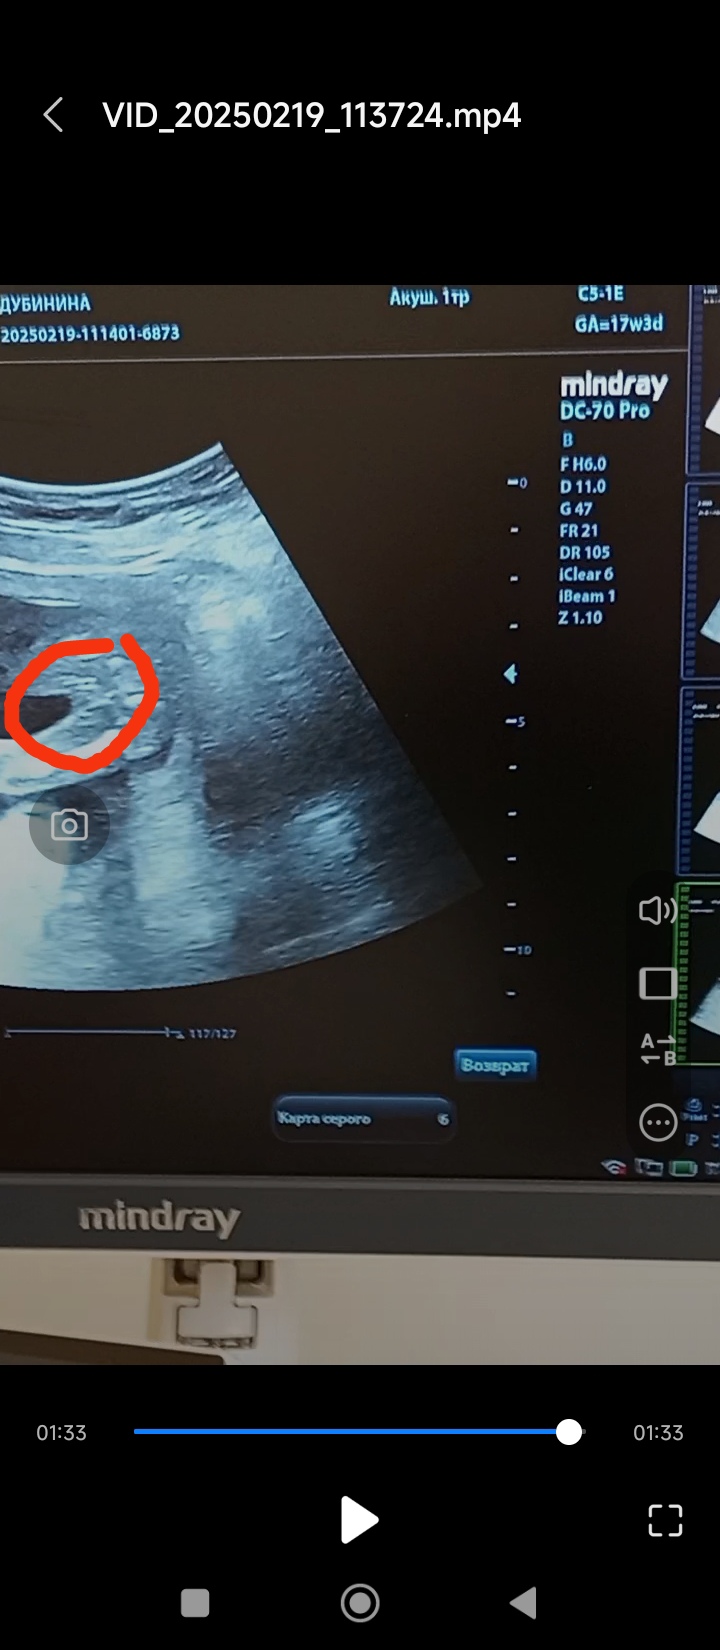

Юлия Мать Драконов, Изображениефото 17 недель.

04.03.2025

А где что на фото? Не понятно что-то 🤔

Не вижу писюна вроде)

Валентина, с пуповиной врач не могла перепутать? на этот фото явно девчачий пирожочек